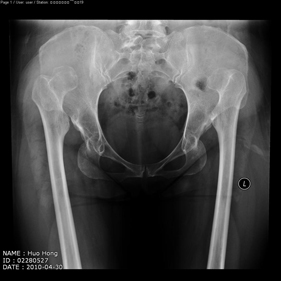

Department of Adult Joint Reconstructive Surgery

shortening osteotomy and total hip replacement for bilateral severe dysplasia of hip with high riding